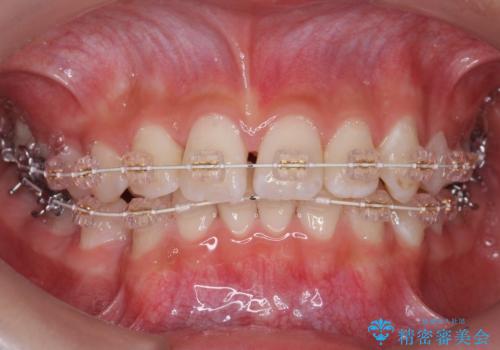

埋まっている犬歯を抜歯して、歯列矯正

- 審美装置

- 右上の犬歯が埋伏していたため、抜歯しました。

その後、右下の小臼歯を1本抜歯し、ワイヤー矯正を行いました。

犬歯の代わりに小臼歯を配列し、最小限の抜歯の本数としました。